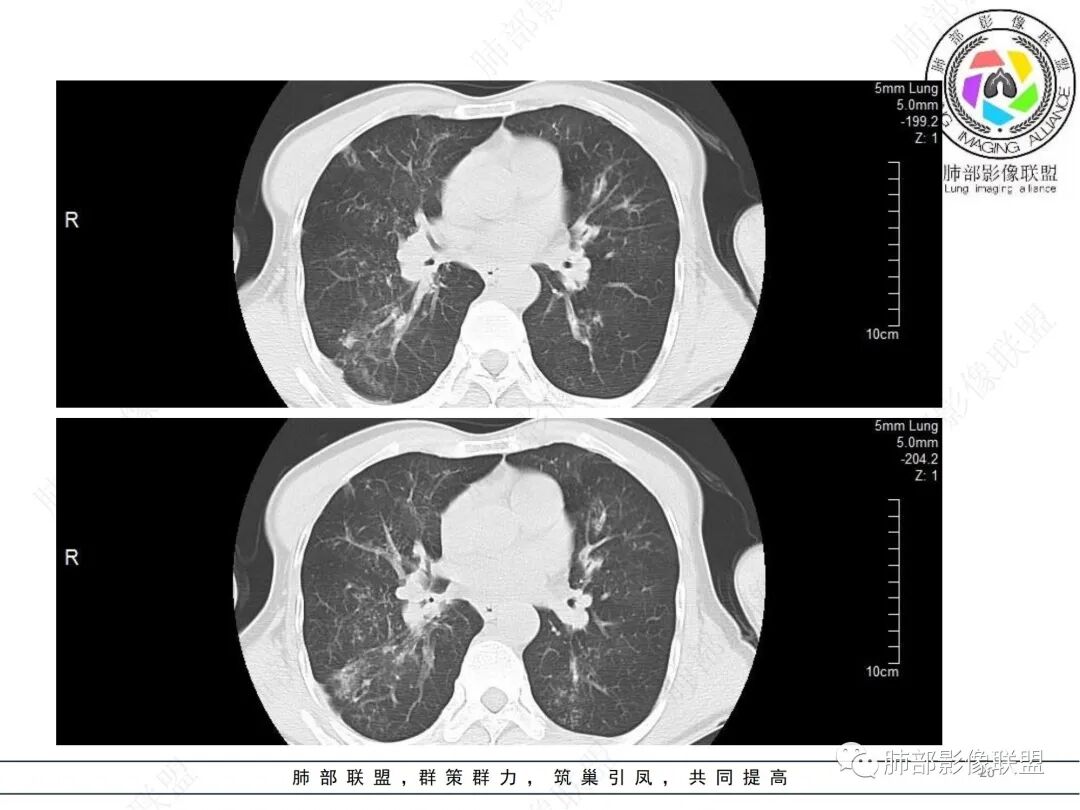

58岁男性,咳嗽胸闷3天,咳较多褐粘液痰,无发热。有2型糖尿病病史。白细胞与中性粒细胞升高。CRP升高。鳞状上皮细胞癌抗原轻度升高。结核T细胞免疫斑点实性阳性。肺炎支原体、衣原体IgG轻度升高。支气管镜显示支气管炎性改变、右肺下叶背段管腔狭窄。2.影像特点:

2022.6.24CT显示两肺弥漫性段、亚段支气管壁增厚(两肺各叶都累及),增厚的支气管壁外可见沿着支气管分布的渗出、实变影。另外远端肺内亦可见多发树芽影、结节影,其边界欠清晰。右肺下叶基底段局部胸膜下亦可见小斑片影,边界不清。2022.6.27CT显示两肺增厚的支气管壁外的渗出实变影明显增多、范围更广。远端肺内病灶亦增多、范围增大。部分位于胸膜下的病灶可见侧向融合趋势。3.病例分析: